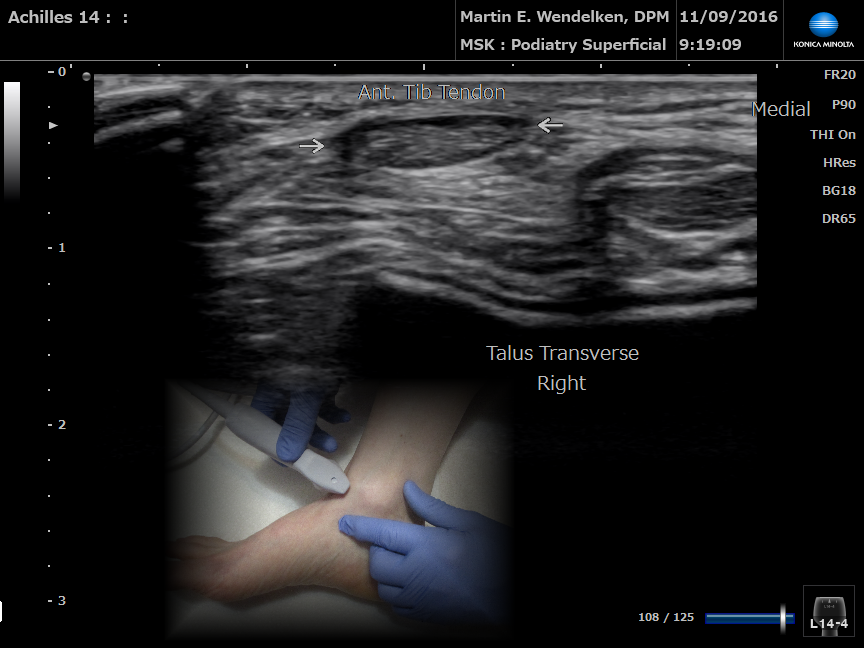

• Image 2: Achilles Tendon